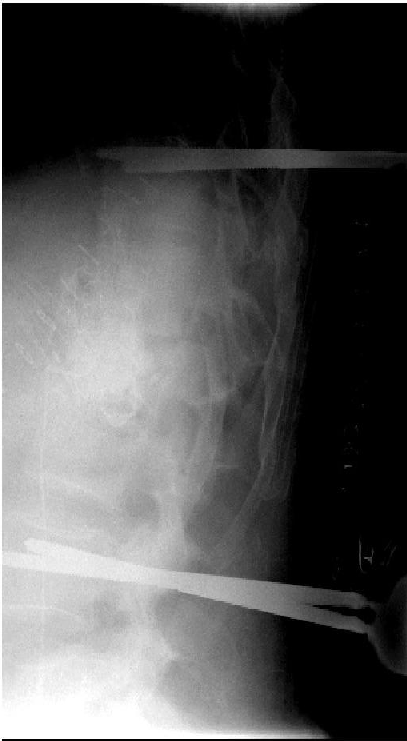

An 84-year-old female patient underwent surgery, due to a progressive kyphotic deformity and spinal cord compression after L1 fracture in severe osteoporosis 8 weeks ago. She was moved to hospital with extended wound necrosis and exogenous vertebral infection after long segment posterior stabilization. The critical soft tissue conditions and septic pedicle screw loosening required a complete implant removal. Because of the large decompression zone, an external spine fixation was necessary to ensure stability. Repetitive surgical debridement, local and systemic antibiotics and vacuum closure therapy led to soft tissue recovery and CRP normalization. The definitive internal stabilization and wound closure occurred after 4 weeks (Figure 8 [Fig. 8], Figure 9 [Fig. 9], Figure 10 [Fig. 10], Figure 11 [Fig. 11], Figure 12 [Fig. 12], Figure 13 [Fig. 13], Figure 14 [Fig. 14]).

Figure 8: L1 compression fracture in severe osteoporosis led to kyphosis and spinal cord compression. Long segment posterior stabilization and multilevel decompression.

Figure 9: The sagittal CT image reveals the extent of the posterior instability.